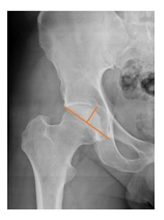

Plain radiographs were evaluated preoperatively and at the most recent follow-up, after appropriate calibration. Positional parameters were assessed according to values guidelines from published literature, as listed in Table 1 [23,24,25,26,27,28,29,30,31]. Femoral stem and acetabular cup osteointegration were quantified according to Engh [32] and Moore scale [33]. Heterotopic ossifications were graded according to the Brooker system [34].

3.4. Radiographic Evaluation

Preoperative and postoperative radiographic data are reported in Table 4. Preoperatively, 18 THR (24.3%) were implanted in skeletally immature children with closed triradiate cartilage (1 ≤ Risser ≤ 3). Radiographic acetabular insufficiency (LCEA < 25° and AI > 13°) was detected in 14 hips (18.9%), while protrusion was present in 3 hips (4.1%) An excessive valgus of the femoral neck was observed in 19 hips (25.7%), while an important varus deformity was present in 7 hips (9.5%).

Postoperative radiographs showed a significant vertical malposition of the cup in 1 case (1.4%), a significant varus stem in 8 cases (10.8%) and a significant valgus stem in 1 case (1.4%). Two patients (2.7%) showed moderate heterotopic bone formation (Brooker ≥ 2), that did not significantly affect the hip motion and symptoms. All those THR that did not undergo revision showed good radiographic osteointegration, with no evidence of implant breakage, radiographic lucencies, bone defects, cup migration, or stem subsidence at the most recent radiographs.

In our experience, implant malposition was the only reason for implant revision. In one case, progressive subsidence was observed in a varus undersized stem, implanted in a boy with Albers–Schömberg disease; in another case, an excessively vertical cup with a 28 mm femoral head caused hip instability and required cup revision.